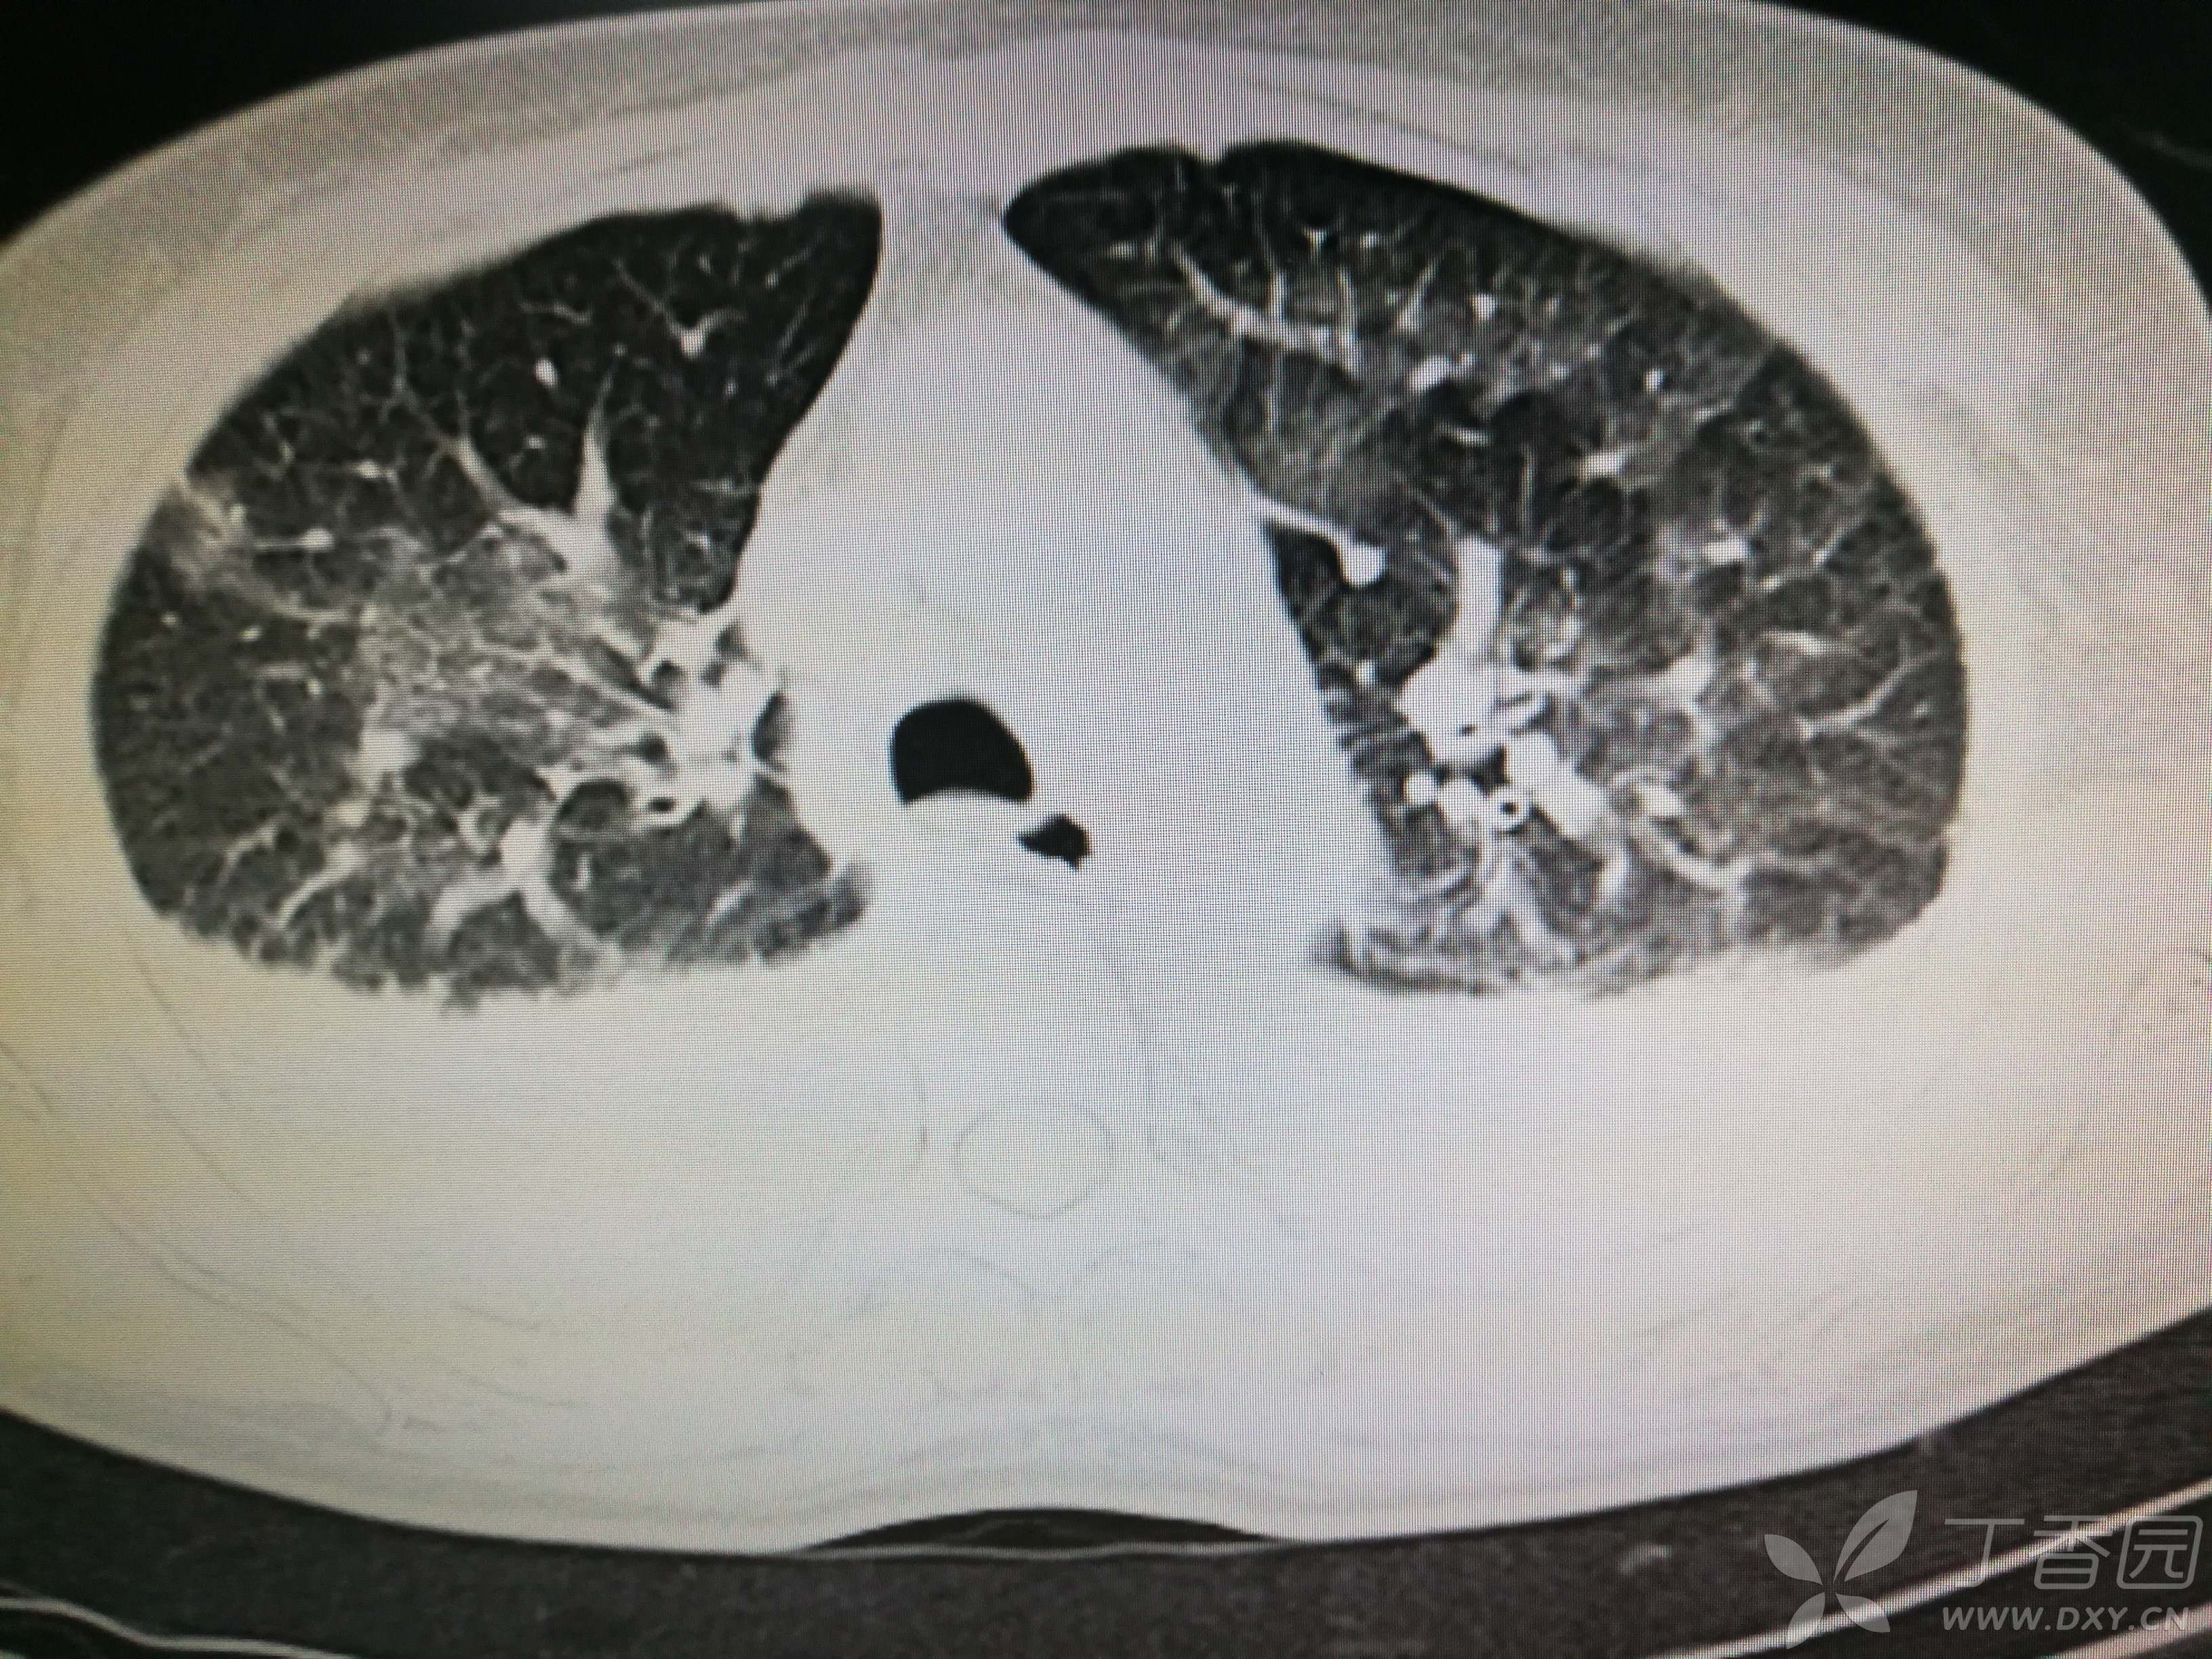

给予低分子肝素钙针抗凝、七叶皂苷钠针消肿及骨牵引固定等等治疗。入院后第四天行“左侧股骨下段骨折切开复位内固定术”(术前查双下肢彩超:双下肢深静脉血流通畅),手术顺利,术后予预防感染、预防血栓形成等治疗。术后患者无明显发热,生命体征平稳。术后第四天复查血常规:白细胞13.4×109/L,血红蛋白84g/L,血小板在正常范围。生化:白蛋白35.7g/L,余无明显异常。当天,患者开始出现轻度胸闷气急,可耐受。术后第五天患者胸闷气急加重,无胸痛,无背痛,无咯血,无意识障碍,无头晕头痛,无恶心呕吐等,急查凝血功能:纤维蛋白原降解产物12mg/L,D二聚体4000ug/L,余无明显异常。查动脉血气分析:pH7.52,氧分压62mmHg,二氧化碳分压30mmHg,碱剩余1.8mmol/L,乳酸1.0mm/L,血红蛋白86g/L。查胸部CT见下(先视频后图片):